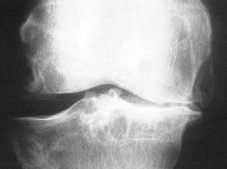

Bei der Arthrose (Bild rechts Kniegelenksarthrose) ist die mechanische Eigenschaft der Gelenkflüssigkeit

erheblich beeinträchtigt.